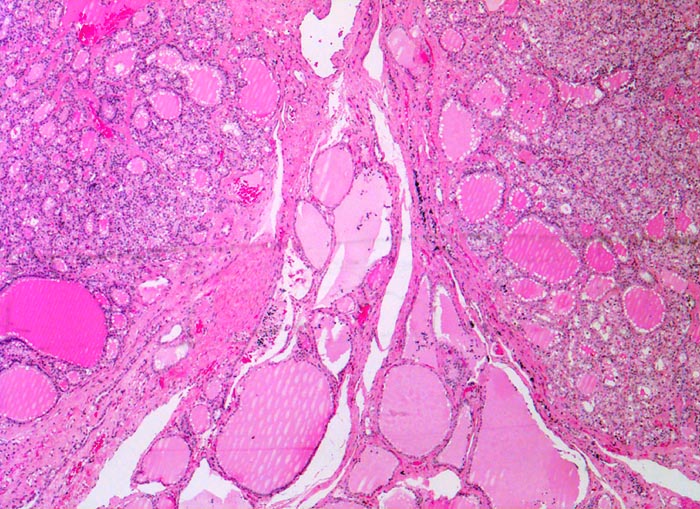

autonomes Adenom

benigner Tumor

Schilddrüse

Zwei scharf begrenzte überwiegend mikrofollikuläre Knoten mit morphologischen Zeichen der gesteigerten hormonellen Aktivität grenzen an atrophes makrofollikuläres Schilddrüsenparenchym in der Bildmitte.

Histologie

25